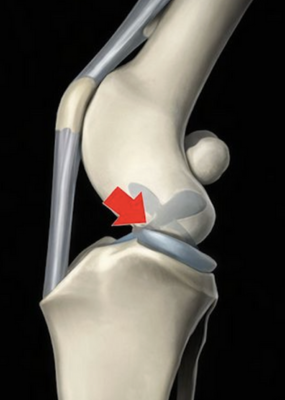

Le chien présente une pente tibiale entrainant lors de rupture de ligament croisé une poussée tibiale craniale et un glissement du fémur caudalement.